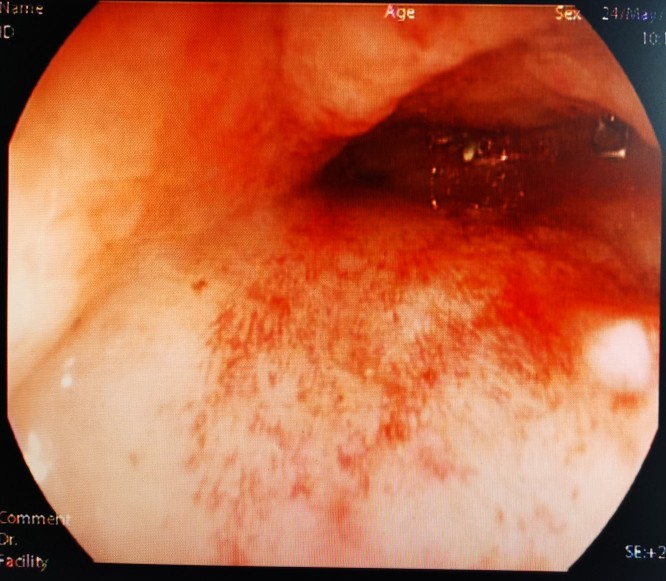

经肛肠镜见吻合口完全闭塞